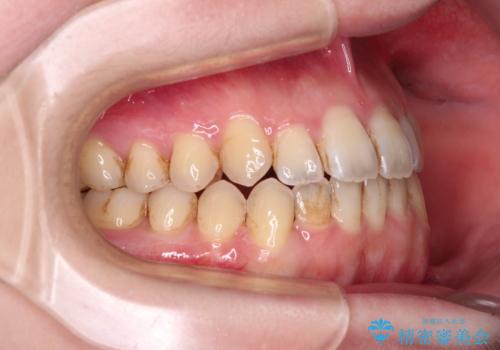

オープンバイトと前歯のデコボコをインビザライン矯正で解消

- 前歯の開咬を気にして来院された患者様です。

開咬の治療は、前歯を閉じるように動かすとともに、上下臼歯を圧下(骨内にめり込ませる)させることで進めて行きます。

インビザラインは臼歯の圧下を効果的に行えるため、インビザラインを用いて矯正治療を行うこととしました。